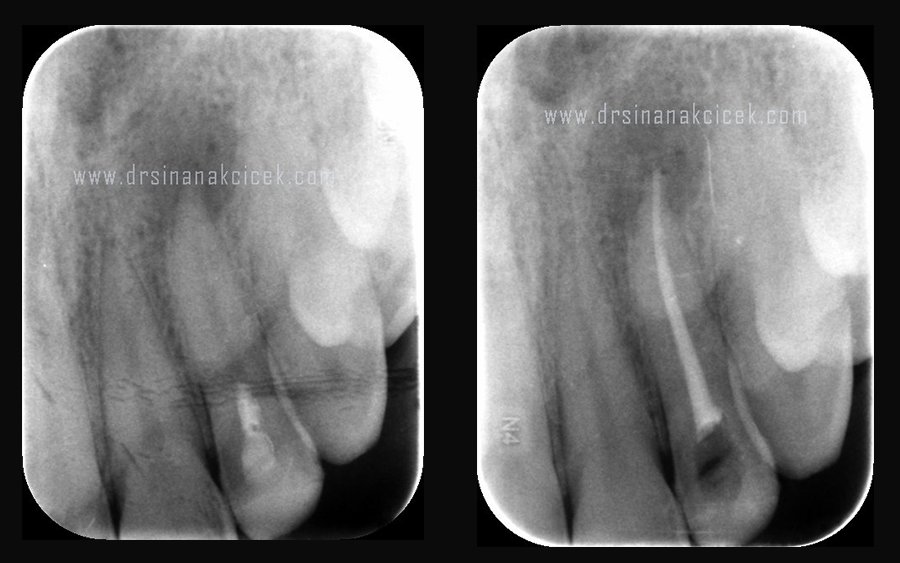

Kanal tedavisinin yenilenmesi daha önceden yapılan kanal tedavisi gibi yapılır, Yenilenme işlemi aşamaları da kanal tedavisine benzerlik gösterir. Kanal tedavisinin yenilenmesi, İlk seansta kanallardaki kök kanal dolgu materyalleri çıkarılır. Yerine bakterileri yok etmek ve enfeksiyonu ortadan kaldırmak için özel ilaçlar yerleştirilip diş geçici dolgu malzemesi ile kapatılır. 7-10 gün sonra bu ilaçlar çıkarılıp kanallar temizlenip kanal dolgusu yapılır. İnatçı enfeksiyon varlığında bu işlem enfeksiyon tamamen ortadan kalkana kadar bir kaç kez tekrarlanır.